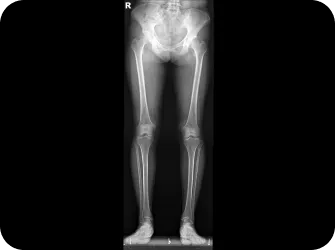

이제는 하세요!

전신 엑스레이 검사

다리길이 엑스레이 검사